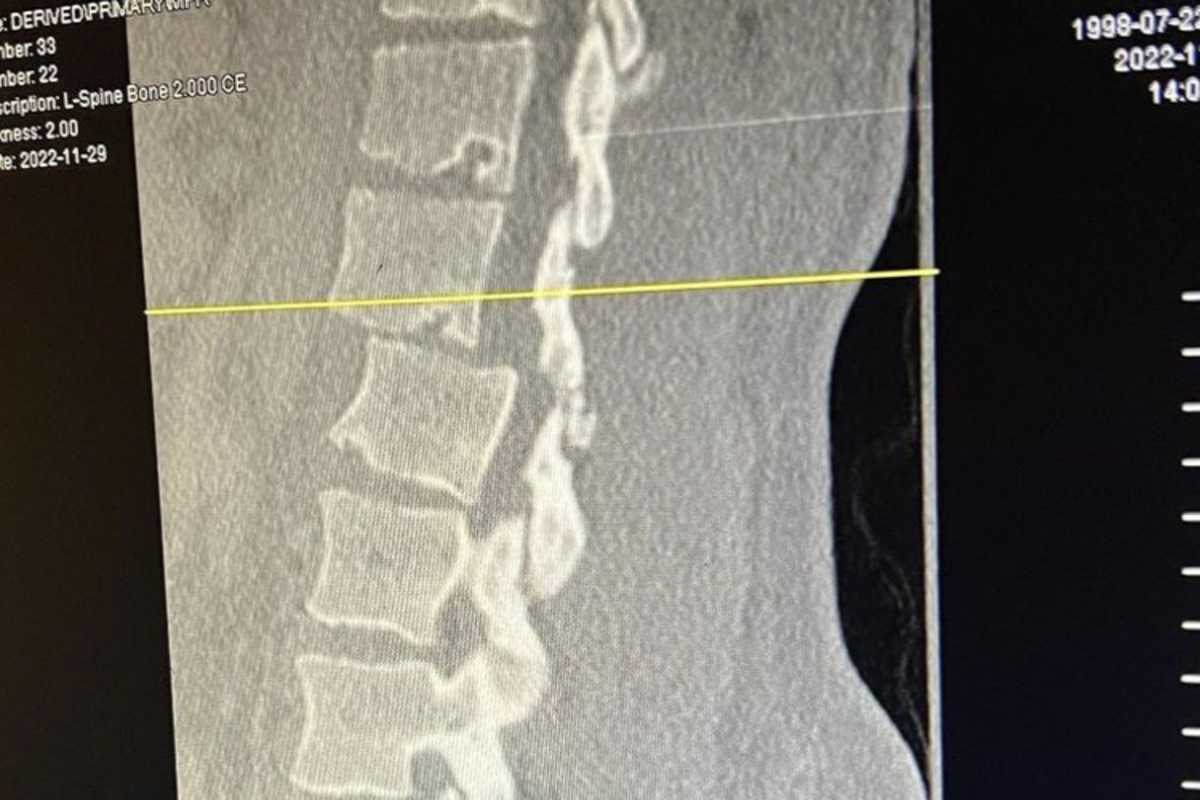

"Es geschah in einer Rhythmussektion von 3 Dreifachsprüngen", erklärte Hartranft. "Ich bin am zweiten Sprung mit dem Kopf voran eingeschlagen." Er zog sich mehrere Wirbelbrüche zu: Die Lendenwirbel L1 und L2 sind gebrochen. Die Querfortsätze der Lendenwirbel L3 und L4 sowie die Dornfortsätze der Lendenwirbel L1, L2 und L3 sind gebrochen. Das linke Hüftgelenk ist ausgekugelt. Außerdem sind mehrere Rippen und das rechte Schulterblatt gebrochen. Zudem hat er einen Hämatothorax erlitten.

Hartranft wurde am Donnerstag operiert, um die Wirbelsäulenverletzungen zu stabilisieren. Sein Zustand ist stabil und hat Gefühl in den Beinen.